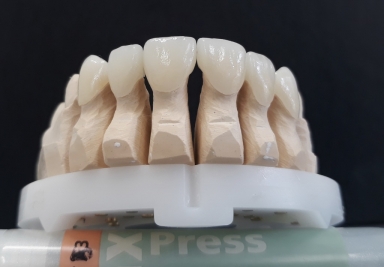

E-max ceramic

E-max ceramic is perfectly identical to natural teeth as you can see in in the pictures.